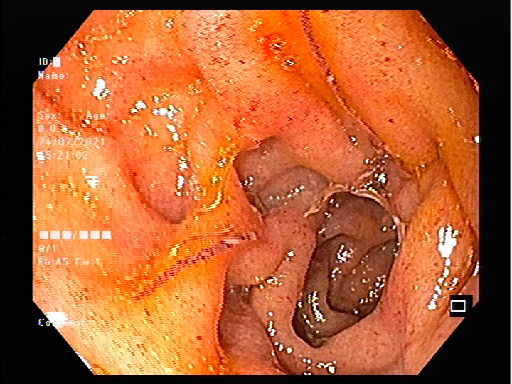

Sau khi thăm khám, qua hình ảnh nội soi, các bác sĩ phát hiện hàng trăm con giun tóc trong đại tràng của bệnh nhân. Ông được dùng thuốc và đang triều trị tại khoa Nội Tim mạch, tình trạng ổn định.

Hình ảnh nội soi đại tràng của bệnh nhân. Ảnh: BVCC.